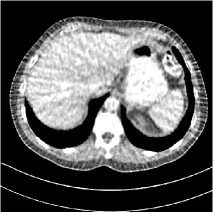

Fig. 3: Three examples (from top to bottom) of the reconstructed testing images using Momentum-Net with SimpleCNN (the second column), with SimpleCNN-RSN (the third column), and with Dn-RSN (the fourth column). The compared WavResNet denoised images are shown in the first column, and the reference images are in the fifth column. See their FBP images in Fig. 4.

Fig. 4: FBP images of test examples.

Fig. 2 shows that the proposed Momentum-Net with SimpleCNN decreases RMSE dramatically in the first 30 layers, and tends to converge in 50 layers. The Momentum-Net reduces the mean RMSE value by 4.5 HU and gives smaller standard deviations in RMSE, compared to WavResNet, as reported in Table 1. This implies that the proposed Momentum-Net with SimpleCNN can improve both the accuracy and stability of low-dose CT image reconstruction than a state-of-the-art image denoising deep NN, WavResNet. The proposed Momentum-Net with SimpleCNN better removes noise and streak artifacts than WavResNet. It also provides clearer reconstructions of some details; see, in Fig. 3, the boundaries shown in the zoomed region at the top-right corner in the first example, the arrow pointed structures in zoomed areas of the second example, and the arrow pointed tissues in the left zoomed region in the third example.

We show the reconstructed examples by Momentum-Net with SimpleCNN-RSN and Dn-RSN in the third and fourth columns of Fig. 3 respectively. Comparing the first three and the last columns in Fig. 3, we observe that Momentum-Net with SimpleCNN-RSN provides generally noisier reconstructions than WavResNet and Momentum-Net with SimpleCNN. However, Momentum-Net with SimpleCNN-RSN sometimes can provide clearer details than WavResNet. For example, in the right zoomed box of the second example, Momentum-Net with SimpleCNN-RSN shows better reconstruction quality for the arrow pointed structures than WavResNet, and in the left zoomed box in the third row, the former gives clearer small tissues marked by red arrows than the latter. Table 1 reports that Momentum-Net with SimpleCNN-RSN is approximately 2.9 RMSE (HU) higher than WavResNet, while it has smaller standard deviations. This implies that Momentum-Net with SimpleCNN-RSN is more stable than WavResNet, although it may not provide better image qualities. Momentum-Net with Dn-RSN, however, provides the worst visual and numerical results among the compared four methods in this paper.